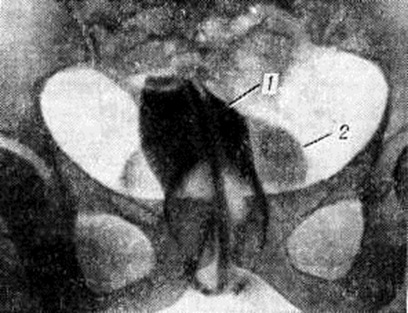

Цистоскопия (смотри полный свод знаний) и хромоцистоскопия (смотри полный свод знаний) позволяют уточнить местоположение пузырного отверстия свища, наличие сопутствующего цистита (смотри полный свод знаний) или камней, взаимоотношение свища с устьями мочеточников и функцию верхних мочевых путей. При точечных и небольших свищах цистоскопия легко осуществима, особенно при использовании постоянного тока жидкости, вводимой в мочевой пузырь. Большие свищи требуют предварительного тампонирования влагалища надувным баллоном или марлевым тампоном, смоченным жидким вазелином. Исследование влагалища с помощью зеркал и цистоскопию можно сочетать с зондированием свища. Рентгенодиагностика везико-вагинальных свищей базируется на цистографии (смотри полный свод знаний) и вагинографии (смотри полный свод знаний Кольпография), которая подтверждает наличие свища и даёт представление о состоянии и ёмкости мочевого пузыря и влагалища (рисунок 1).

Рис. 1.

Кольпограмма больной с везико-вагинальным свищом: 1 — влагалище; 2 — мочевой пузырь, заполненный контрастным веществом через свищ из влагалища.